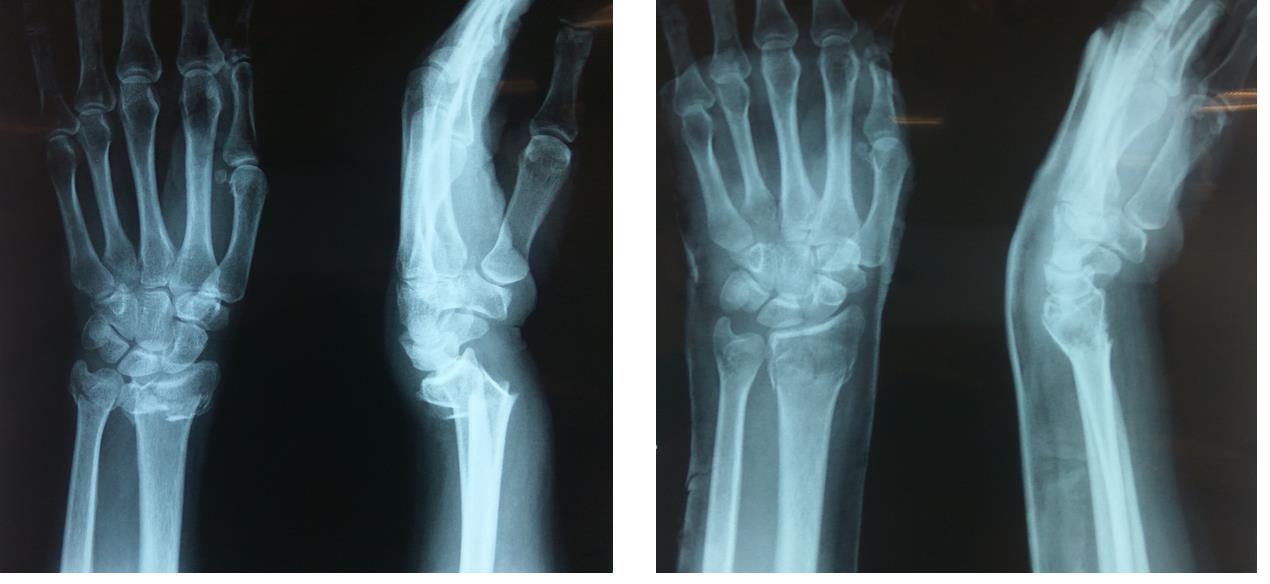

Ниже приведен пример перелома, который так и не зажил должным образом (перелом без сращения). Первый снимок — несращенный перелом пациента. На втором снимке — исцеленная рука.